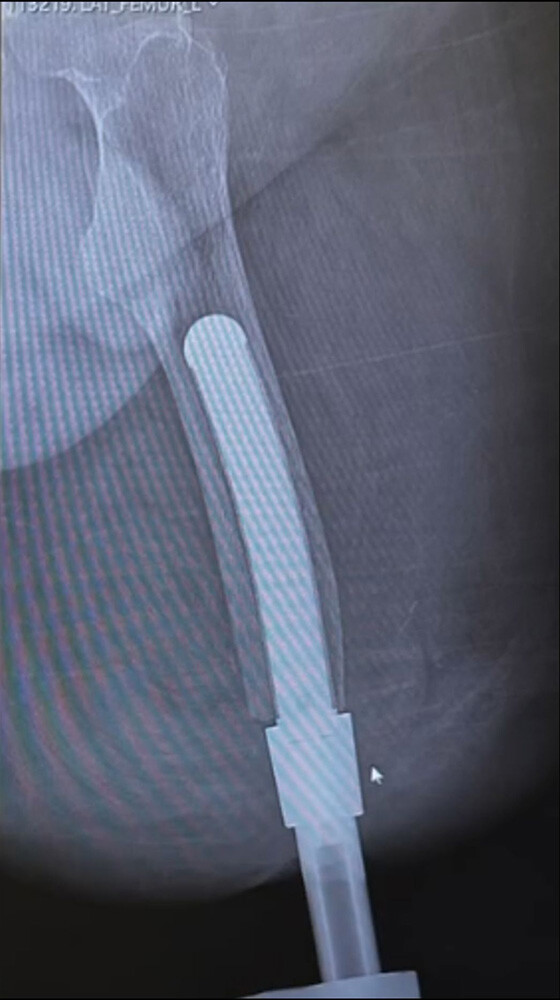

Our work begins with a consultation with the surgeon and CT scan modeling of the patient’s anatomy.

This is the basis for a design tailored to the patient and digital manufacturing.

Advanced osseointegration is designed into every implant. Our manufacturing process allows geometry and surface texture to be tuned to encourage bone growth for maximum fixation. We are osseointegration specialists.